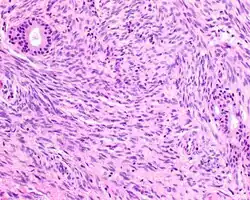

A high-power view of a hematoxylin- and eosin-stained slide showing respiratory epithelial inclusions within a spindled cell neoplasm showing characteristics of a biphenotypic sinonasal sarcoma

Hematoxylin and eosin stained image of a biphenotypic sinonasal sarcoma

• Infiltrative, highly cellular spindled cell neoplasm is poorly circumscribed and unencapsulated. Bone destruction or invasion is common. The cells show medium to long fascicles (nerve fibers), with a herringbone pattern. The cells are remarkably uniform with elongated nuclei. Delicate strands of intercellular collagen without ropy or dense deposition are seen. A very characteristic concurrent surface-type respiratory epithelial proliferation is found from the surface or in small cystic spaces around the cancer cells, often forming glands. The background may have a rich vascularity and usually has a small number of scattered lymphocytes. Extra growths or mitoses are rare, while necrosis, ulceration, and hemorrhage are usually absent.